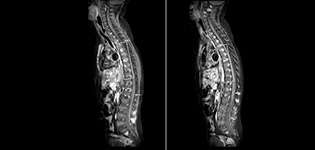

Fat saturation is historically challenging at the ends of fields of view, especially in total spine imaging and in difficult patient anatomy such as the lower regions of the neck. “Due to the unique fat suppression capabilities of mDIXON, however, these challenges no long apply,” says Dr. Miller. “We routinely obtain homogeneous fat suppression under virtually all conditions. It has also led to some efficiencies by not having to repeat sequences because of that technical failure.”

mDIXON TSE makes a difference

“mDIXON TSE is most useful in patients with lesions or abnormalities in the soft tissues such as the face and neck, and for patients with contrast enhancing abnormalities that are mostly visible with fat suppression,” says Dr. Miller. “All our spine imaging now routinely contains mDIXON water-only T2 images, and this allows us to identify pathology that may be obscured by non-fat suppressed imaging such as injuries of the bone. And it’s not necessary to obtain additional standard TSE T2 images because the in-phase mDIXON images are equivalent to standard TSE T2 images.”

“mDIXON TSE has increased our diagnostic confidence in ruling in or ruling out abnormalities in which fat suppression is critical to diagnosis, such as metastatic disease or osseous abnormalities.”